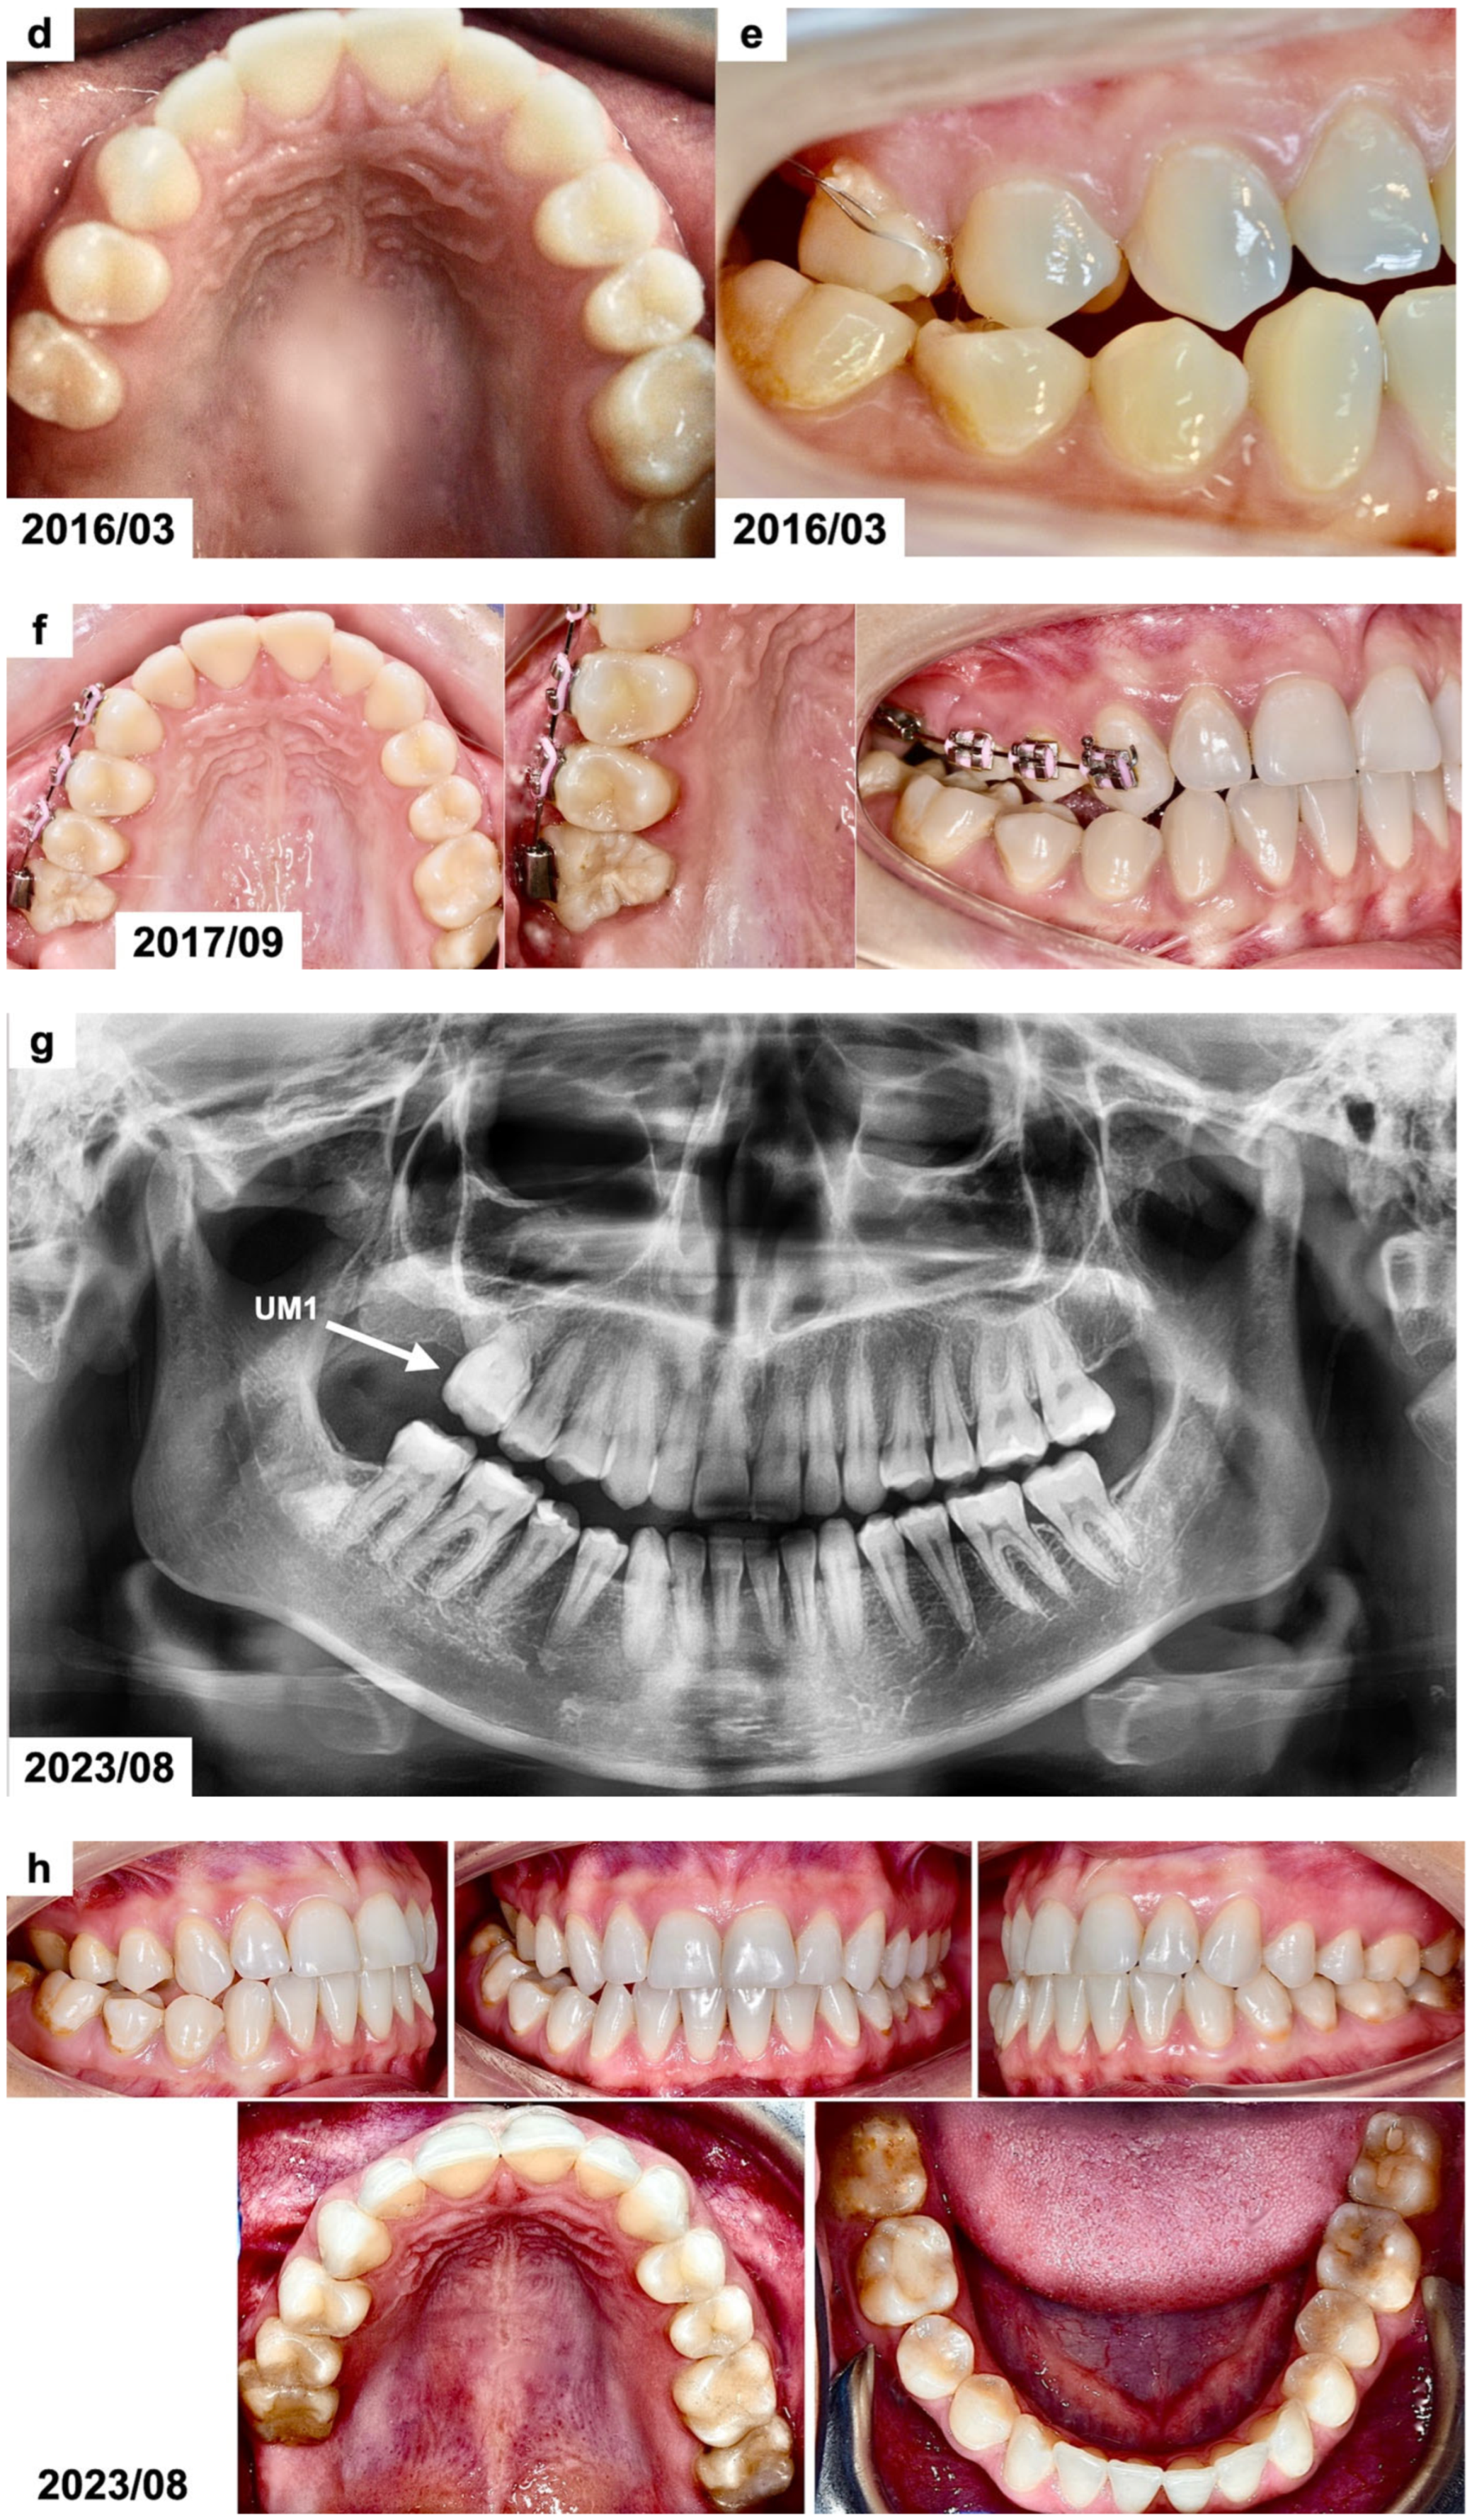

Figure 2.

(a) CBCT examination scans before the treatment presenting the odontogenic tumor in the right maxillary molar region. The patient was 15 years and 10 months old. (b) CBCT examination scans after the surgical removal of the tumor presenting the malposition of the impacted permanent upper right first molar. The patient was 16 years and 4 months old. (c) Panoramic radiograph after the treatment, presenting the impacted maxillary. The patient was 16 years and 7 months old. (d,e) Intraoral photographs 10 months after the surgical treatment before the use of orthodontic traction with a segmented fixed appliance. The patient was 16 years and 7 months old. (f) Intraoral photographs 1 year and 4 months after the orthodontic traction of the permanent upper right first molar. The patient was 17 years and 10 months old. (g) Panoramic radiograph 6 years after the surgical and orthodontic treatment. The patient was 24 years and 1 month old. (h) Intraoral photographs 6 years after the surgical and orthodontic treatment showing the erupted permanent upper right first molar and its position in the dental arch. The patient was 24 years and 1 month old. (i) CBCT examination scans 6 years after the surgical and orthodontic treatment presenting the erupted permanent upper right first molar and the absence of the alveolar bone at the site of the tumor removal. The patient was 24 years and 1 month old.

The treatment plan included surgical removal of the tumor and a combined surgical and orthodontic extrusion of the impacted maxillary molar. Bonding of an orthodontic button with a soft ligature for orthodontic traction was planned during the surgical removal of the tumor. The patient was not interested in the comprehensive orthodontic treatment to correct the posterior crossbite. Therefore, a segmented fixed orthodontic appliance in the maxillary posterior segment on the right side was planned, including the canine and both premolars. The orthodontic traction of the impacted molar was planned after the surgical removal of the tumor and lack of a spontaneous eruption. The patient was negative regarding the use of any temporary skeletal anchorage devices (TADs) from the start of orthodontic traction.

The result of a histopathological examination with H&E staining revealed the presence of mature tubular dentin with the spaces containing small amounts of enamel matrix or immature enamel—the mature enamel was removed during the decalcification process. Therefore, based on the clinical, radiological, and histological examinations, the diagnosis of a complex odontoma was confirmed. The impacted maxillary molar was left for observation, but no signs of its spontaneous eruption were seen for 10 months (Figure 2c–e). Therefore, an orthodontic traction with a segmented fixed appliance was planned (0.022 slot, American Orthodontics, Mini Master series). Orthodontic brackets were bonded on the maxillary canine and premolars on the right side. The teeth were aligned after 3 months, and a stainless-steel rectangular wire (0.017 × 0.022 SS) was placed. The impacted tooth was attached to the appliance using an elastomeric Powerchain attached to the metal ligature. The Powerchain was scheduled for changing every 5–6 weeks. The impacted molar was successfully extruded in the oral cavity after 1 year and 4 months (Figure 2f); however, the patient missed some appointments. The patient refused to continue her orthodontic treatment to correct the posterior crossbite after the extrusion of the impacted molar. The orthodontic appliance was debonded, and no retention was used. The patient missed scheduled follow-up appointments and presented for re-evaluation 5 years after finishing the orthodontic traction. The maxillary right first molar was present in the oral cavity without any signs of pathology (Figure 2g,h). The cone-beam computed tomography revealed the absence of the alveolar bone at the site of the tumor removal. It was recommended to perform bone augmentation procedures before further implantation (Figure 2i).